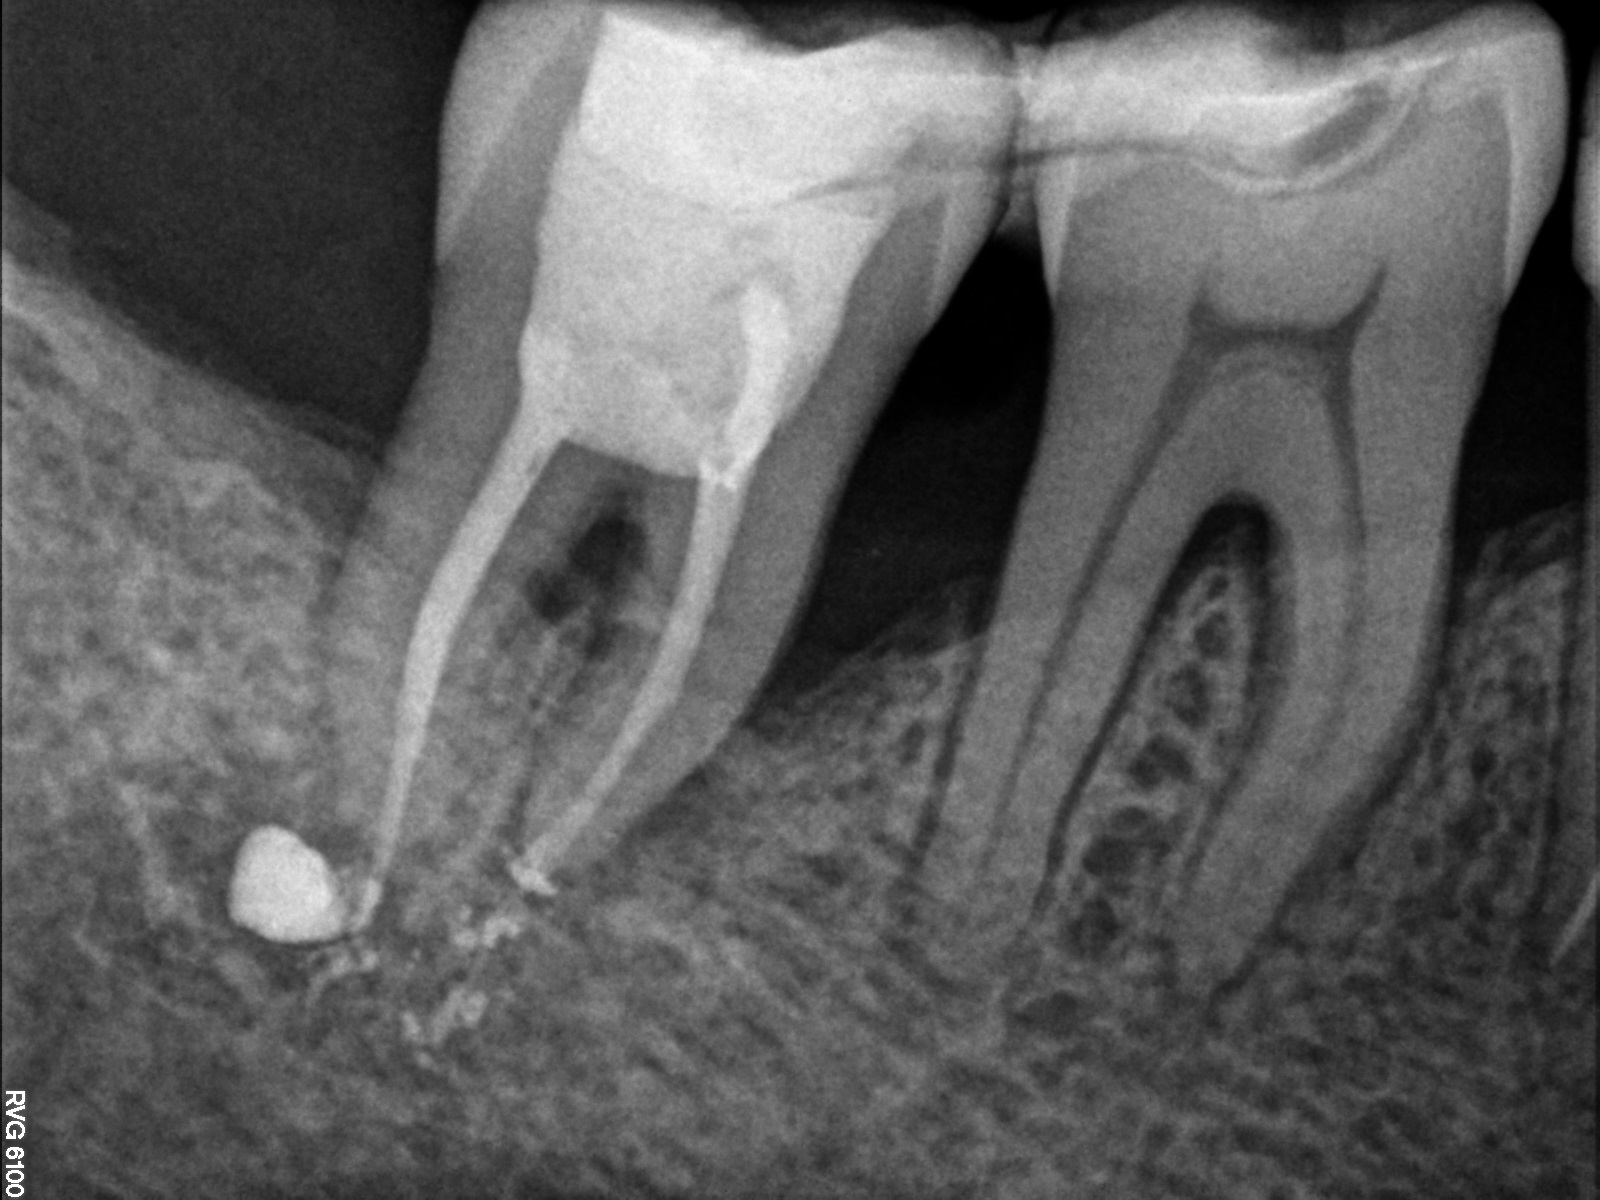

Bogata w płytki i leukocyty fibryna jest stosowana w regeneracji tkanek od ponad 15 lat. Pozytywny wpływ PRF (platelet-rich fibrin) na regenerację tkanek miękkich jest niewątpliwy, bezsporny i częściowo udowodniony w badaniach klinicznych i analizach biochemicznych. Wpływ PRF na regenerację tkanki kostnej jest obserwowany klinicznie, ale nadal niedostatecznie poznany jest mechanizm tego zjawiska.

Platelet- and leukocyte-rich-fibrin has been used in regeneration of tissue for more than 15 years. The positive influence of PRF on the regeneration of soft tissue is undoubtedly, without question and partially proven in clinical studies and biochemical analysis. Influence of PRF on regeneration of bone tissue is observed clinically but the mechanism of this phenomenon is still not sufficiently known.